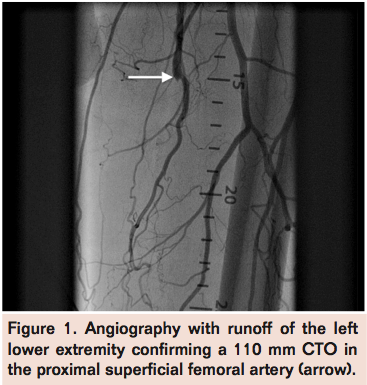

A 69-year old male with history of coronary artery disease presented with lifestyle-limiting claudication of the left lower extremity. Physical examination revealed non-palpable left dorsalis pedis and posterior tibial pulses, which were both present on Doppler. Angiography with runoff of the left lower extremity confirmed a 110 mm chronic total occlusion (CTO) in the proximal superficial femoral artery (Figure 1), with reconstitution of the distal superficial femoral artery via collaterals (Figure 2) and 3-vessel runoff into the left foot.